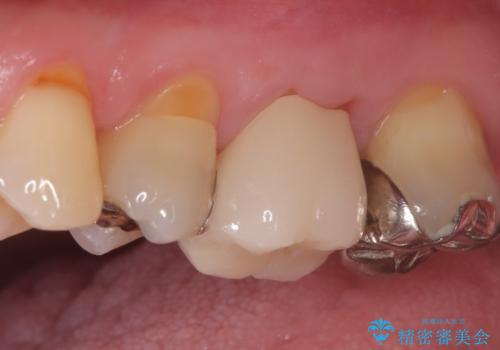

他院で治らなかった根管治療を精密治療で改善|MB2を発見し再治療

- 患者様は、他院で根管治療を受けていたが、なかなか治らず、より精密な治療を希望して当院を受診されました。マイクロスコープを使用して詳しく診断したところ、上顎第一大臼歯(6番)のMB2(第二頬側根管)の見落としが判明。このままでは感染が残り、再発のリスクが高い状態であるため、当院で精密根管治療を行う方針としました。

マイクロスコープを使用してMB2を確認し、感染源を徹底的に除去。その後、根管内を清掃・消毒し、高品質な充填材で密閉しました。従来の根管治療では見落とされがちなMB2の発見により、治療の精度が大幅に向上し、炎症の改善が期待できる状態となりました。患者様からは「治療後の違和感がなくなり、しっかり噛めるようになった」と喜びの声をいただきました。